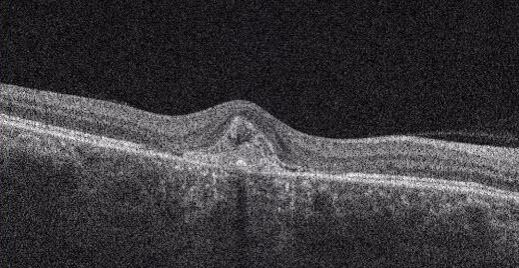

01.三次元眼底画像解析装置(OCT)

網膜の断面を観察して、網膜やその下の新生血管などの状態を立体的に観察します。